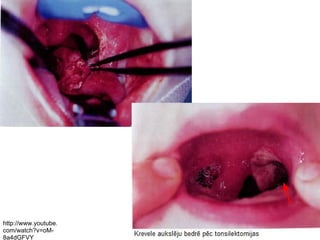

Ķirurģiskā ārstēšana =

tonsilektomija

● pilnīga vienas vai abu mandeļu

izgriešana kopā ar kapsulu

http://www.youtube.

com/watch?v=oM-

8a4dGFVY

Ķirurģiskā ārstēšana = tonsilektomija ●pilnīga vienas vai abu mandeļu izgriešana kopā ar kapsulu